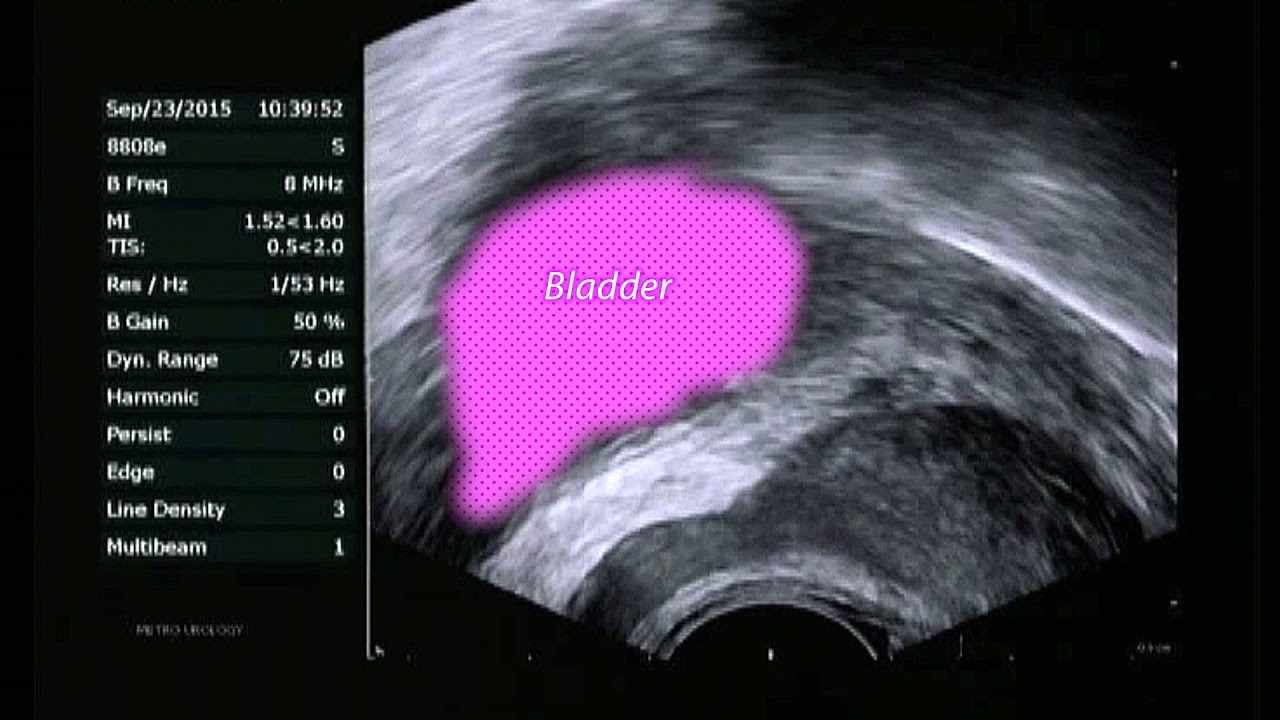

The doctor’s approach is to give a single 10 cc shot of lidocaine, he said he watches via ultrasound image to ensure it spreads to both sides.

This video sponsored by Boston Scientific recommends two shots of lidocaine, each 10 cc, also ultrasound guided: